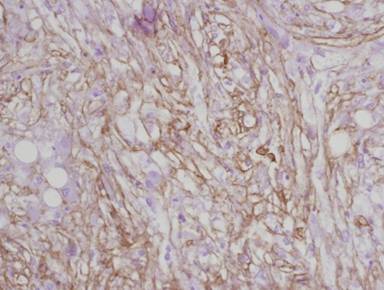

Pathological analysis of the specimens revealed a well-circumscribed vascularized neoplasm, measuring 32x27x30 mm, composed of epithelioid smooth muscle cells with clear cytoplasm rich in glycogen (Figure 1). The tumor exhibited immunoreactivity to alpha-smooth muscle actin (Figure 2) and to melanoma-associated antigen HMB-45 (Figure 3), but not to the epithelial marker, cytokeratin. The tumor displayed high nuclear pleomorphism but no mitotic figures were seen in 50 high power fields (HPF) and the proliferative index Mib1 (Ki67) was less than 1%. No tumor was detected at the surgical margins or in the 14 regional lymph nodes resected.

Figure 2. The tumor exhibits positive immunoreactivity to smooth muscle actin (magnification x200). |